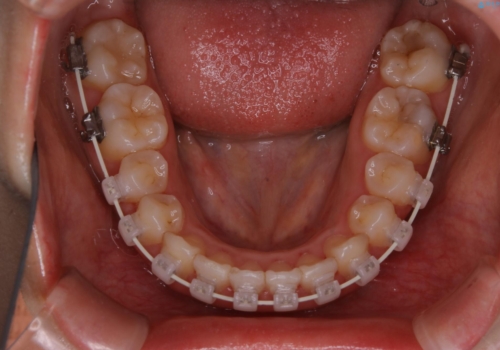

- 矯正装置

- ワイヤー審美装置

- 治療計画

- 4年ほど前から地元の歯科医院にてインビザライン治療を行っていたが、引っ越し後に通いづらくなってしまったため、治療が途中で止まってしまっているとの事で来院されました。性格的にインビザラインの継続した使用が難しいとのことで、ワイヤー装置にて最終仕上げを行いました。

治療について

インビザラインは20時間以上の装着を厳守して頂くことで治療効果が期待できる治療となります。固定式のワイヤー装置に切り替えることで短期間で歯並びを整えることができ、大変喜んでいただけました。